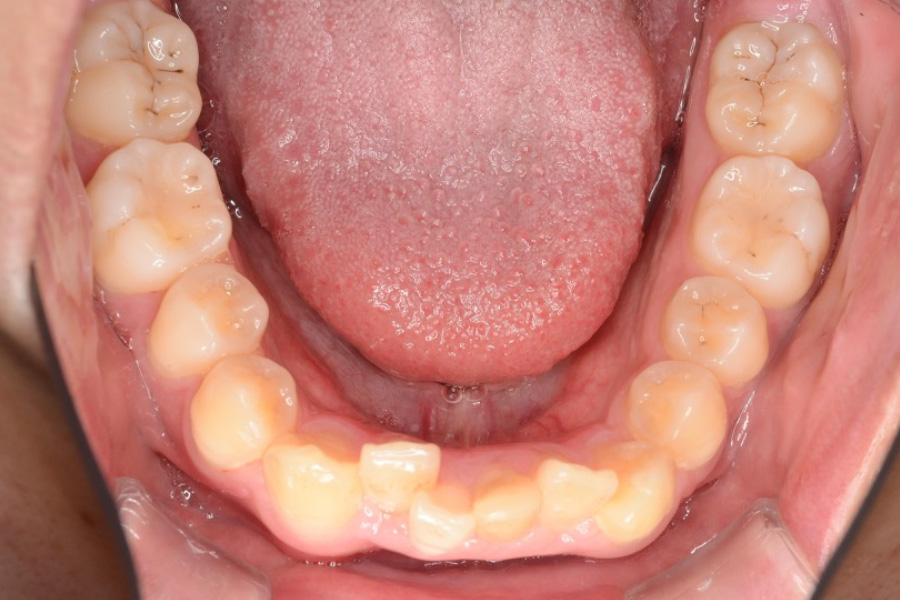

治療前

主訴 突出感、ガタつきが気になる